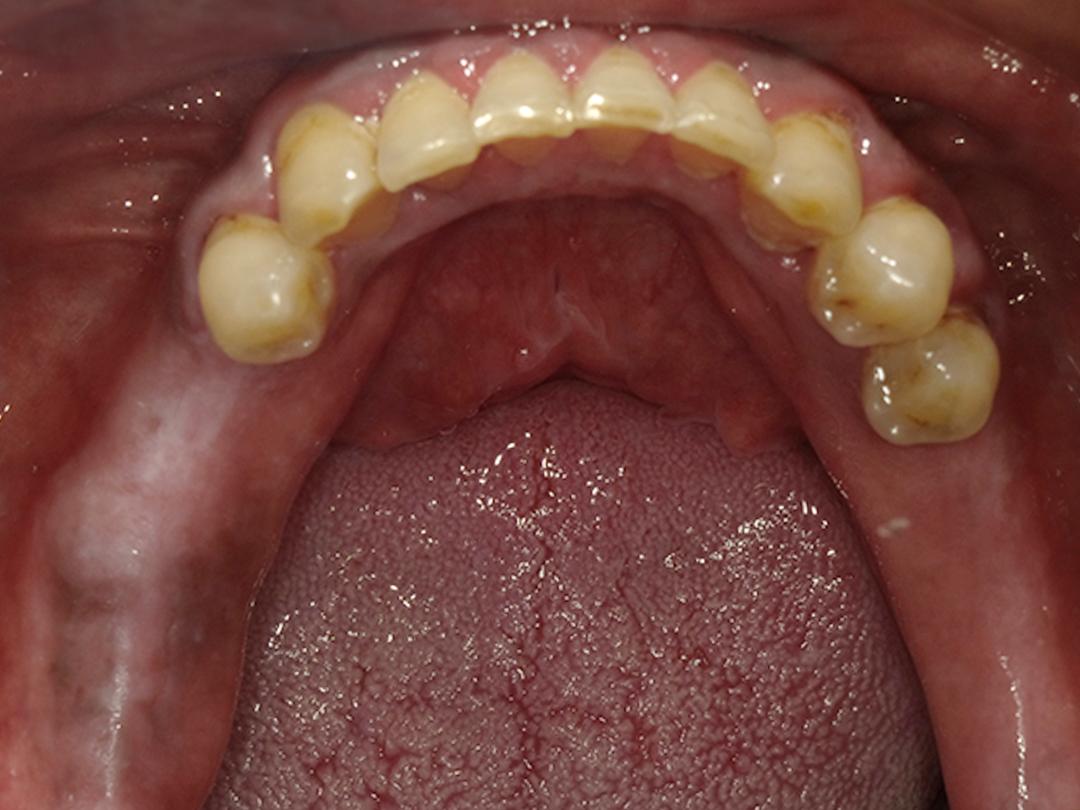

下顎智能AI模擬

下顎左右兩邊四顆植牙一次完成